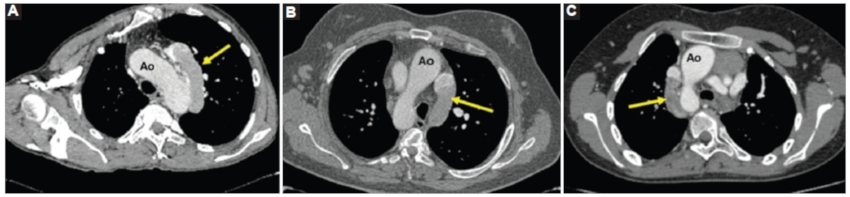

Alteraciones vasculares

La alteración más frecuentemente asociada es la interrupción de la VCI retrohepática con continuación como vena ácigos o hemiácigos, hallazgo que se observa en todos los casos (Fig. 5). Esta alteración puede ser sugerida por la radiografía de tórax, como en el caso 1, en el que se observó ausencia de la VCI en el sector posteroinferior de la silueta cardiaca en el enfoque lateral y el cayado de la ácigos prominente en la proyección frontal (Fig. 6).

La VCI infrarrenal discurrió normalmente a la derecha de la aorta, hasta la desembocadura de ambas venas renales en los casos 3 y 4. En el caso 1 presenta un recorrido a la izquierda de la aorta. Luego continuó como vena ácigos aumentada de tamaño, formando un prominente cayado de la ácigos, a la derecha en el caso 3 y a la izquierda en los casos 1 y 2 (Fig. 7).